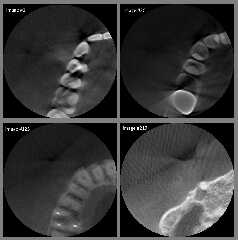

I have attached a sample of my original DICOM images (as converted to

8-bit .png) just to show what the problems are. I think that the images you are

using are of *much* higher quality.

In my opinion, my dentist needs to purchase an improved CT scanner! ;-)

Your media images from your earlier post definitely look much nicer than mine.

The main problem I am having is that the original DICOM images from my own CT

scan are *extremely* noisy and of low quality; it is even difficult to see what

is 'organic matter' and what is just noise. And the exposure level from image to

image seems to change at random, which I suspect is a result of the CT's x-rays

being 'auto-compensated' for changes in bone density (or whatever!)